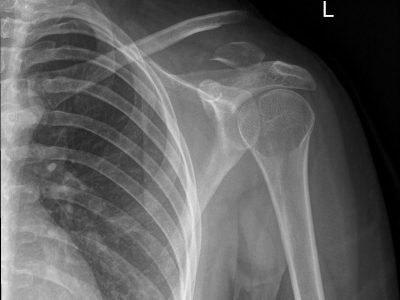

Παρακάτω παρατίθενται ακτινογραφίες καταγμάτων του άνω άκρου που αντιμετωπίζονται με εσωτερική οστεοσύνθεση ή επανορθωτική χειρουργική με αρθροπλαστική.